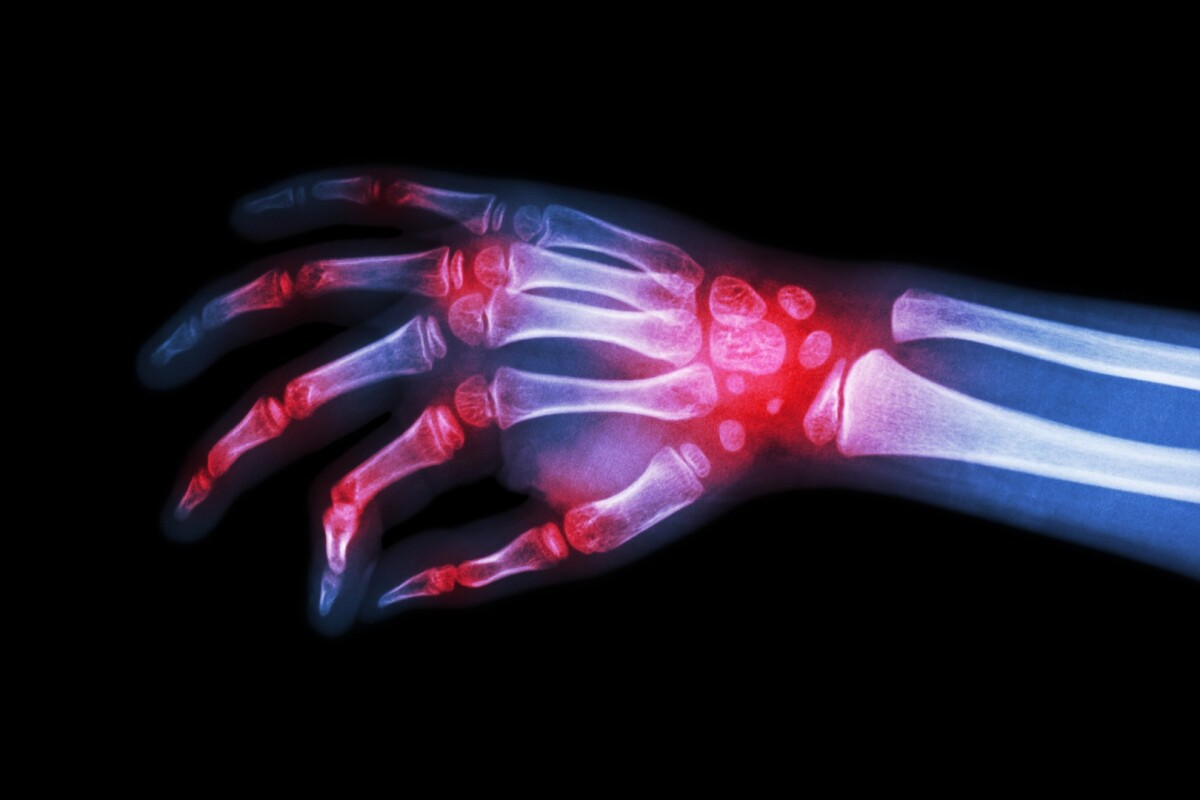

Arthritis Drug Breakthrough . London scientists have discovered a way to reverse inflammation and arterial blockages in rheumatoid arthritis, paving the way for better treatments for the condition. People with rheumatoid arthritis (ra) could soon benefit from a new drug treatment that not only suppresses inflammation but also. Long term relief is within reach for people with the debilitating autoimmune disease, rheumatoid arthritis (ra), after an $11.5 million. The results of the clinical trial show methotrexate, a medication already used for autoimmune conditions, to be effective in. Results from a phase 2b clinical trial, published today in the lancet by researchers led by king's college london, provides hope for. Researchers have discovered that rvt4, a molecule, significantly boosts the body’s defenses against atherosclerosis in rheumatoid arthritis patients by enhancing macrophages’ ability to reduce inflammation and clear vascular blockages. Results from a phase 2b clinical trial, published today in the lancet by researchers led by king’s, provides hope for arthritis.

People with rheumatoid arthritis (ra) could soon benefit from a new drug treatment that not only suppresses inflammation but also. The results of the clinical trial show methotrexate, a medication already used for autoimmune conditions, to be effective in. Long term relief is within reach for people with the debilitating autoimmune disease, rheumatoid arthritis (ra), after an $11.5 million. Researchers have discovered that rvt4, a molecule, significantly boosts the body’s defenses against atherosclerosis in rheumatoid arthritis patients by enhancing macrophages’ ability to reduce inflammation and clear vascular blockages. Results from a phase 2b clinical trial, published today in the lancet by researchers led by king’s, provides hope for arthritis. Results from a phase 2b clinical trial, published today in the lancet by researchers led by king's college london, provides hope for. London scientists have discovered a way to reverse inflammation and arterial blockages in rheumatoid arthritis, paving the way for better treatments for the condition.